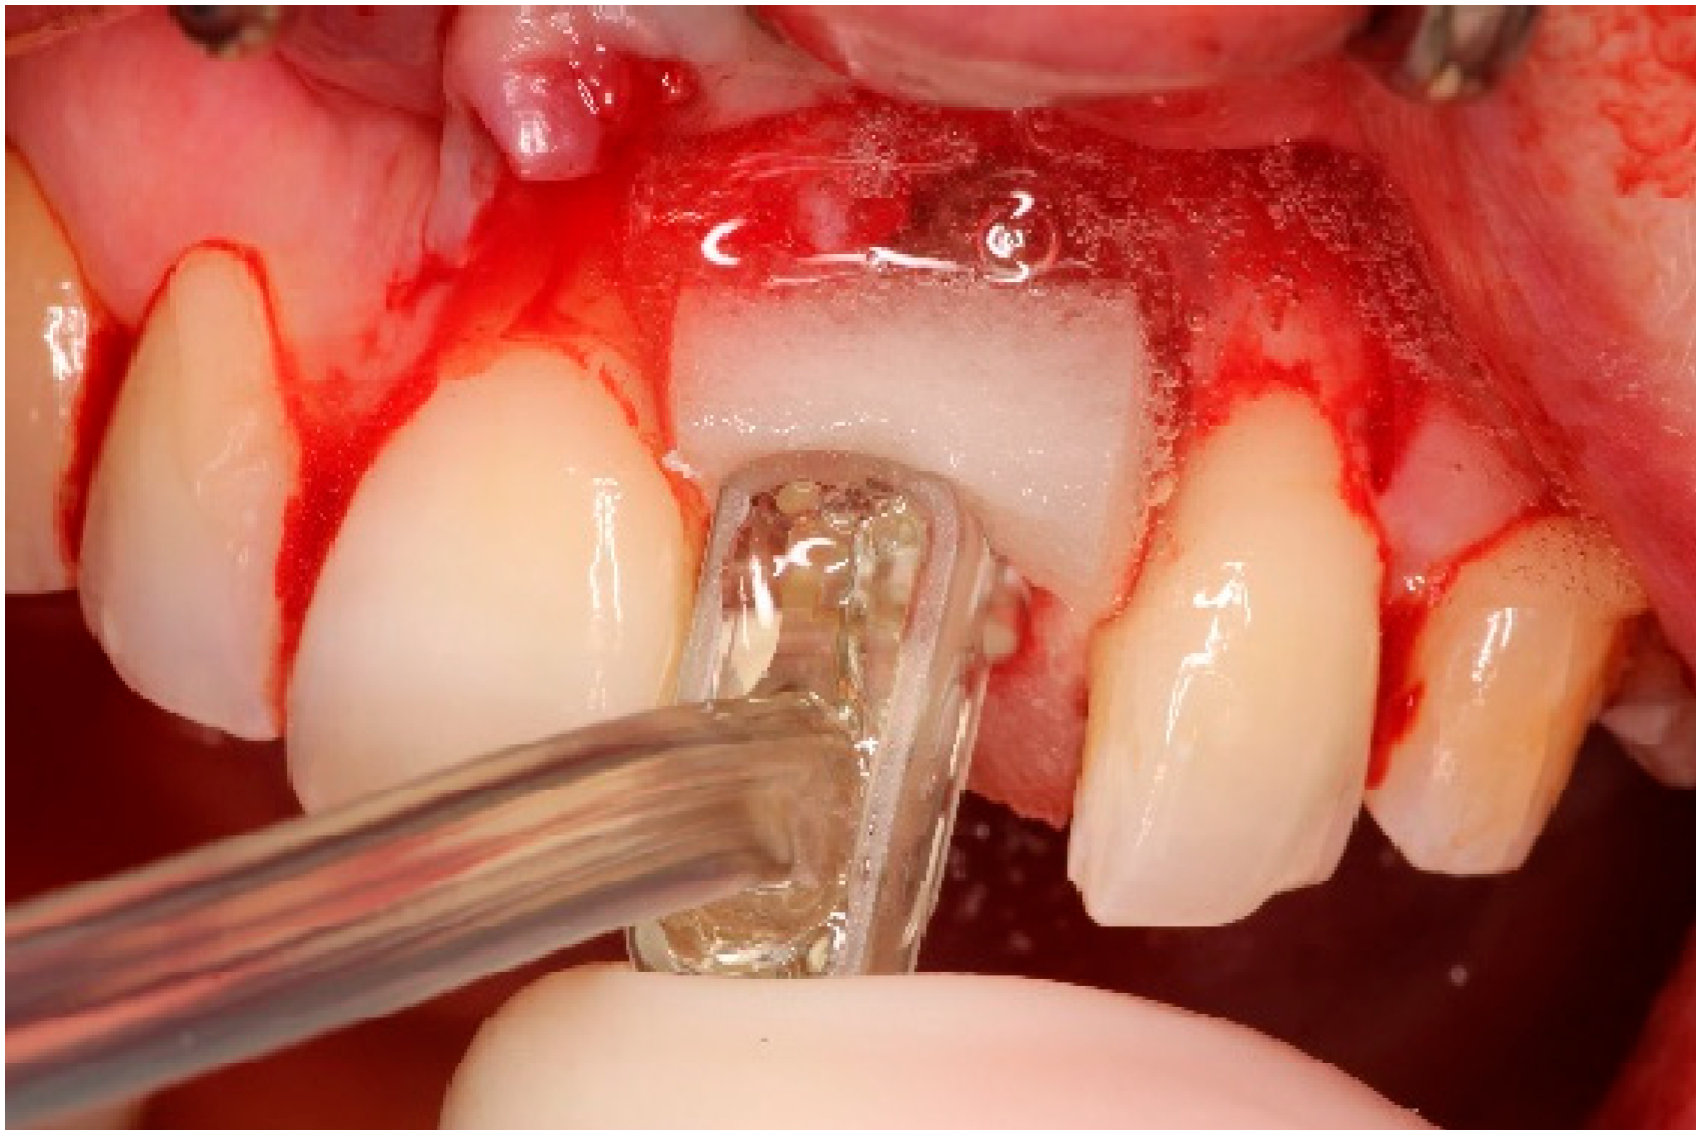

4. Timeline and Diagnostic Assessment

5. Therapeutic Intervention

5.3. Surgical Treatment